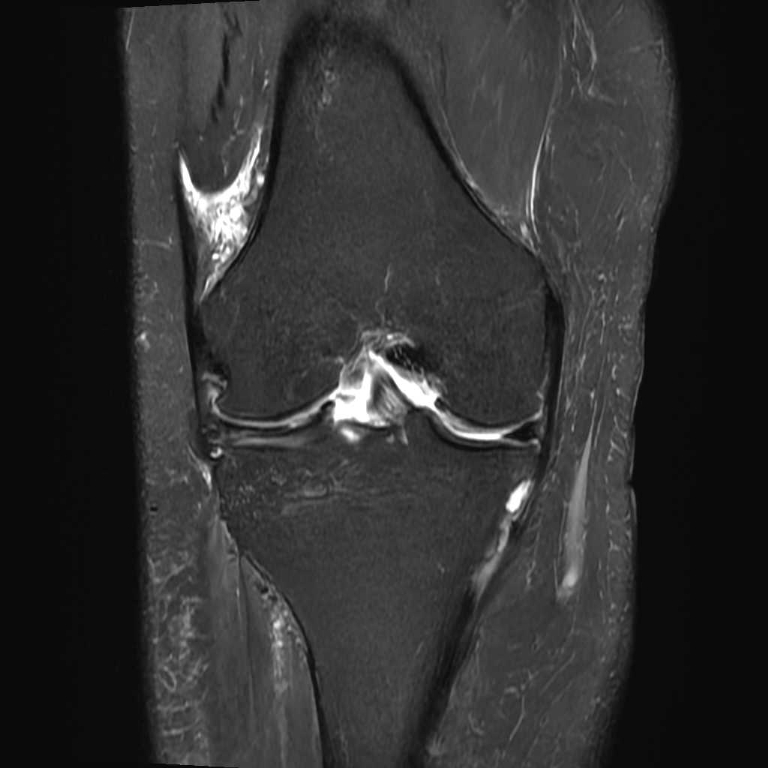

整形外科領域

膝関節

半月板損傷